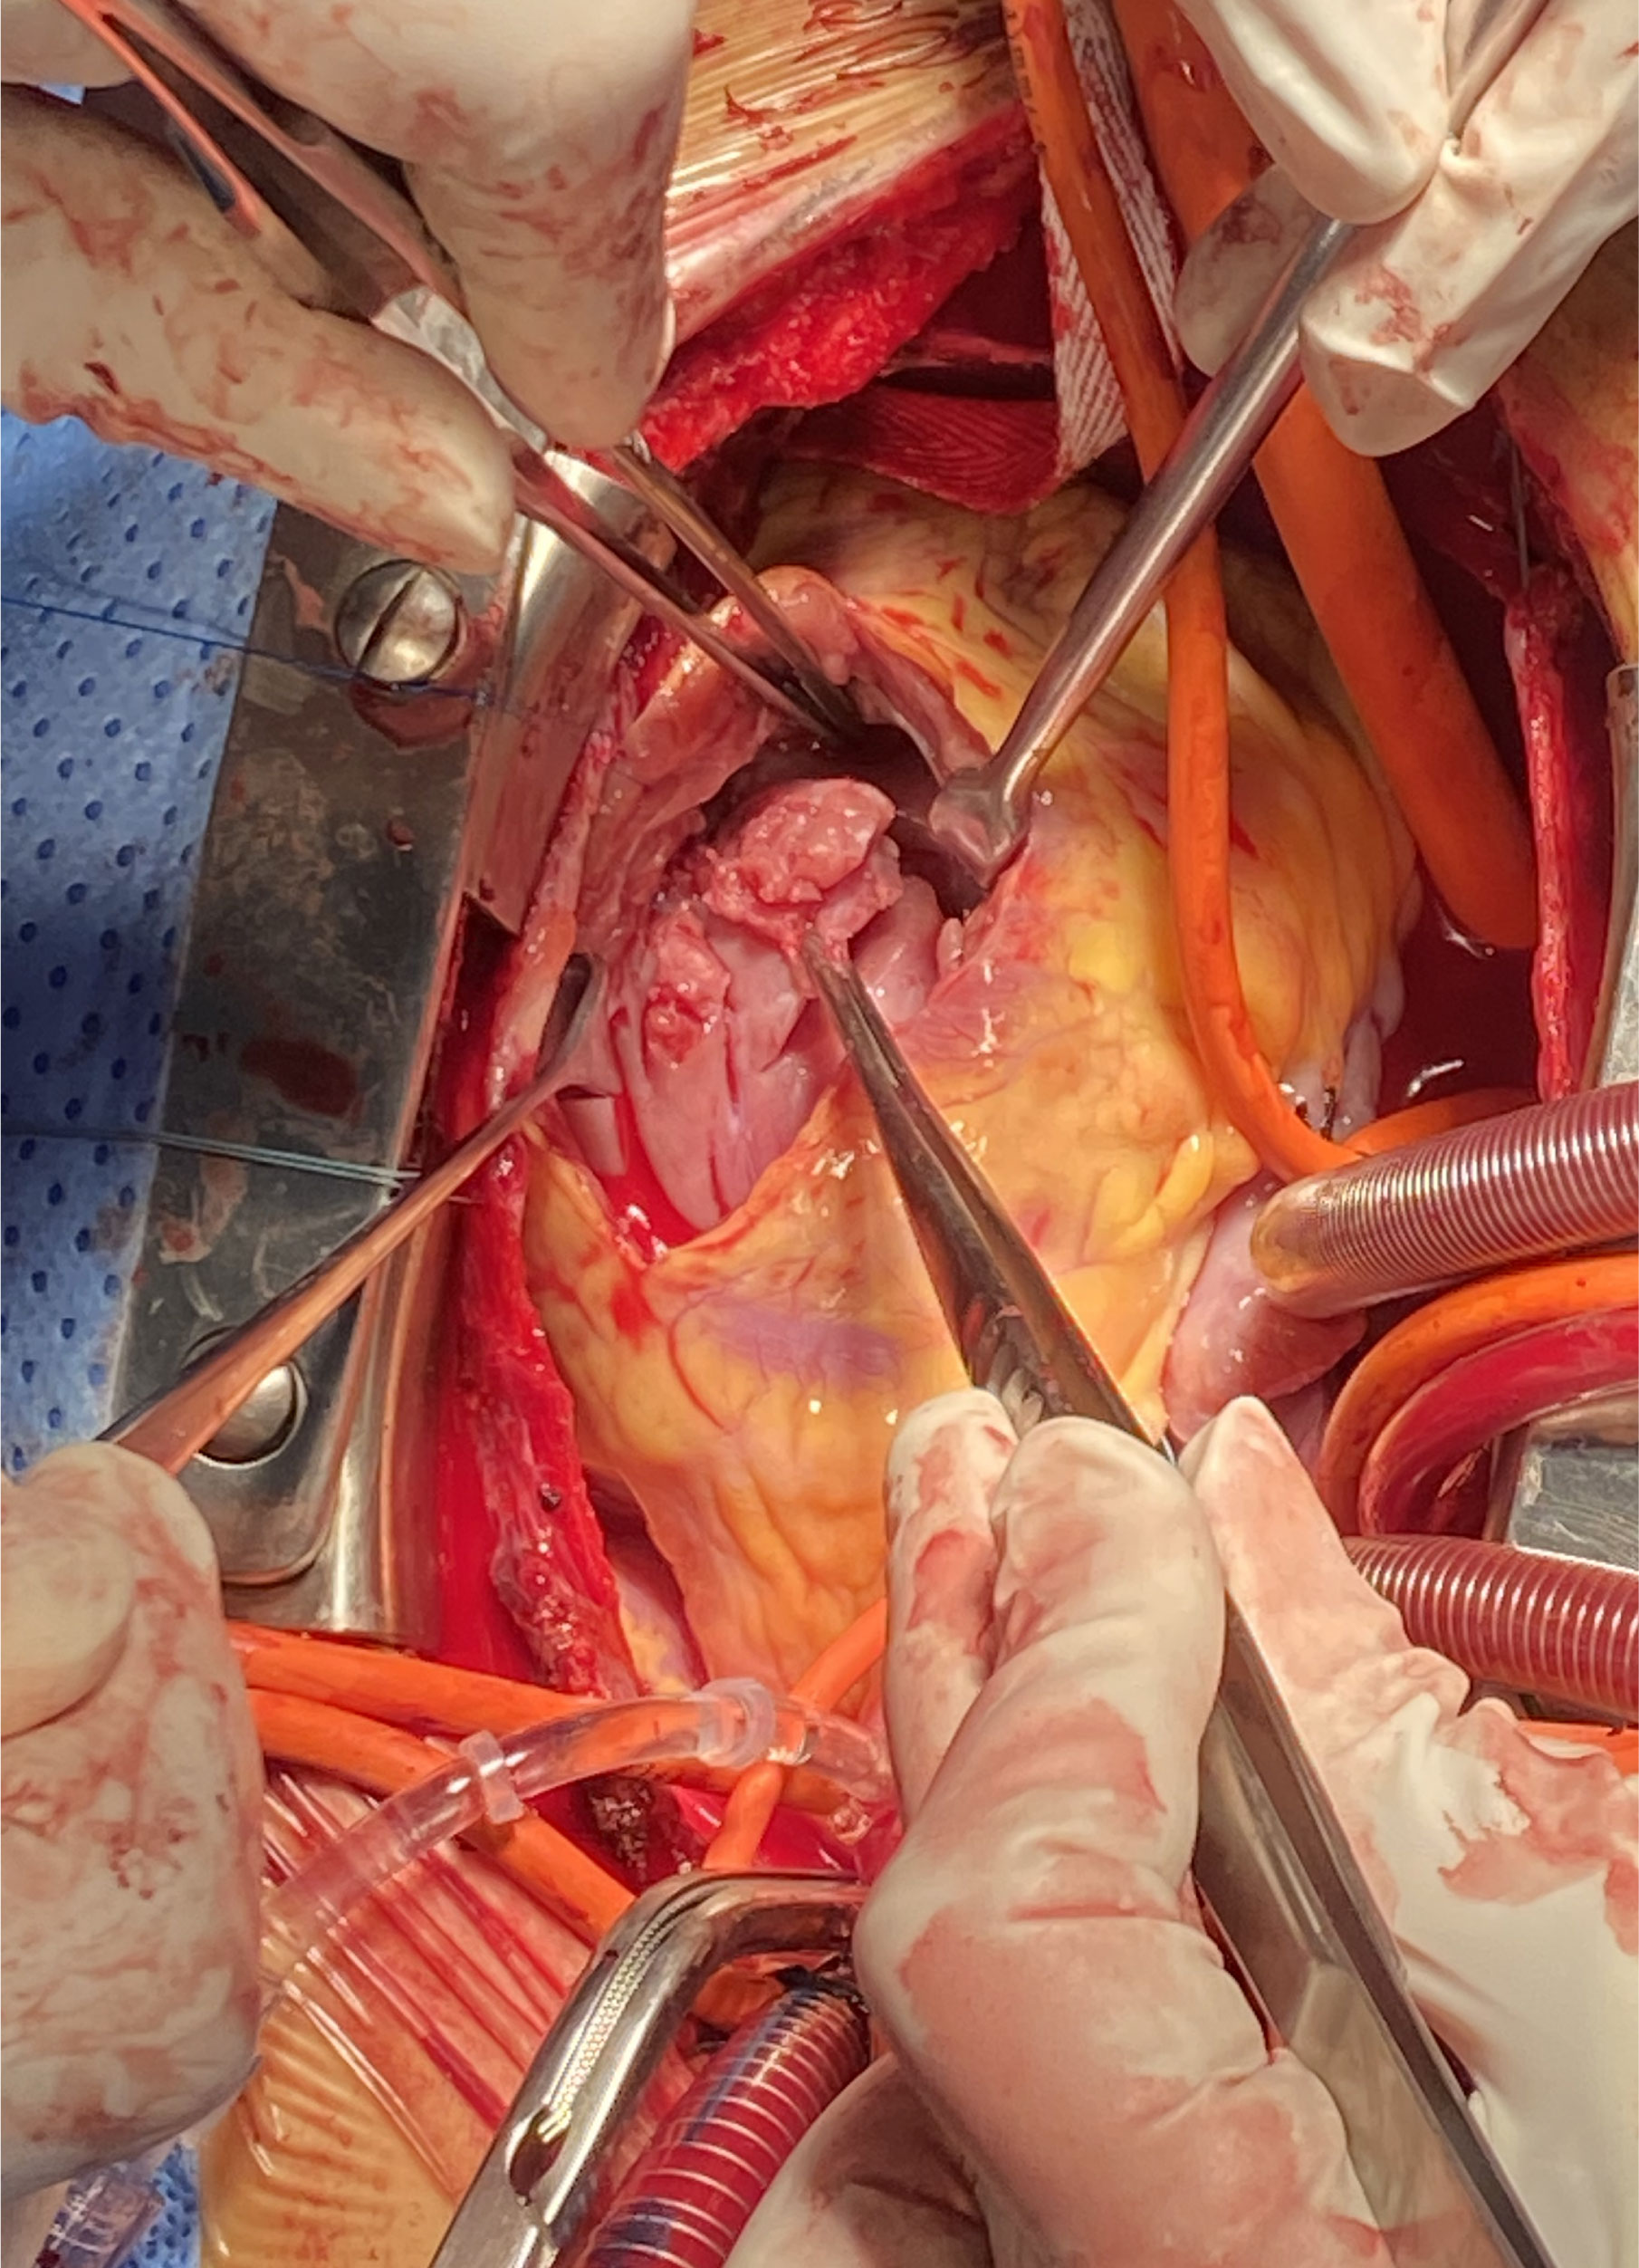

Background: Right ventricular

involvement in hypertrophic cardiomyopathy is uncommon. This study aimed to

evaluate clinical outcomes of the modified septal myectomy in patients diagnosed

with biventricular hypertrophic cardiomyopathy (BHCM), a subject seldom explored

in the literature. Methods:

enrolling 12 patients with BHCM. Each patient underwent

a modified

septal myectomy and was followed